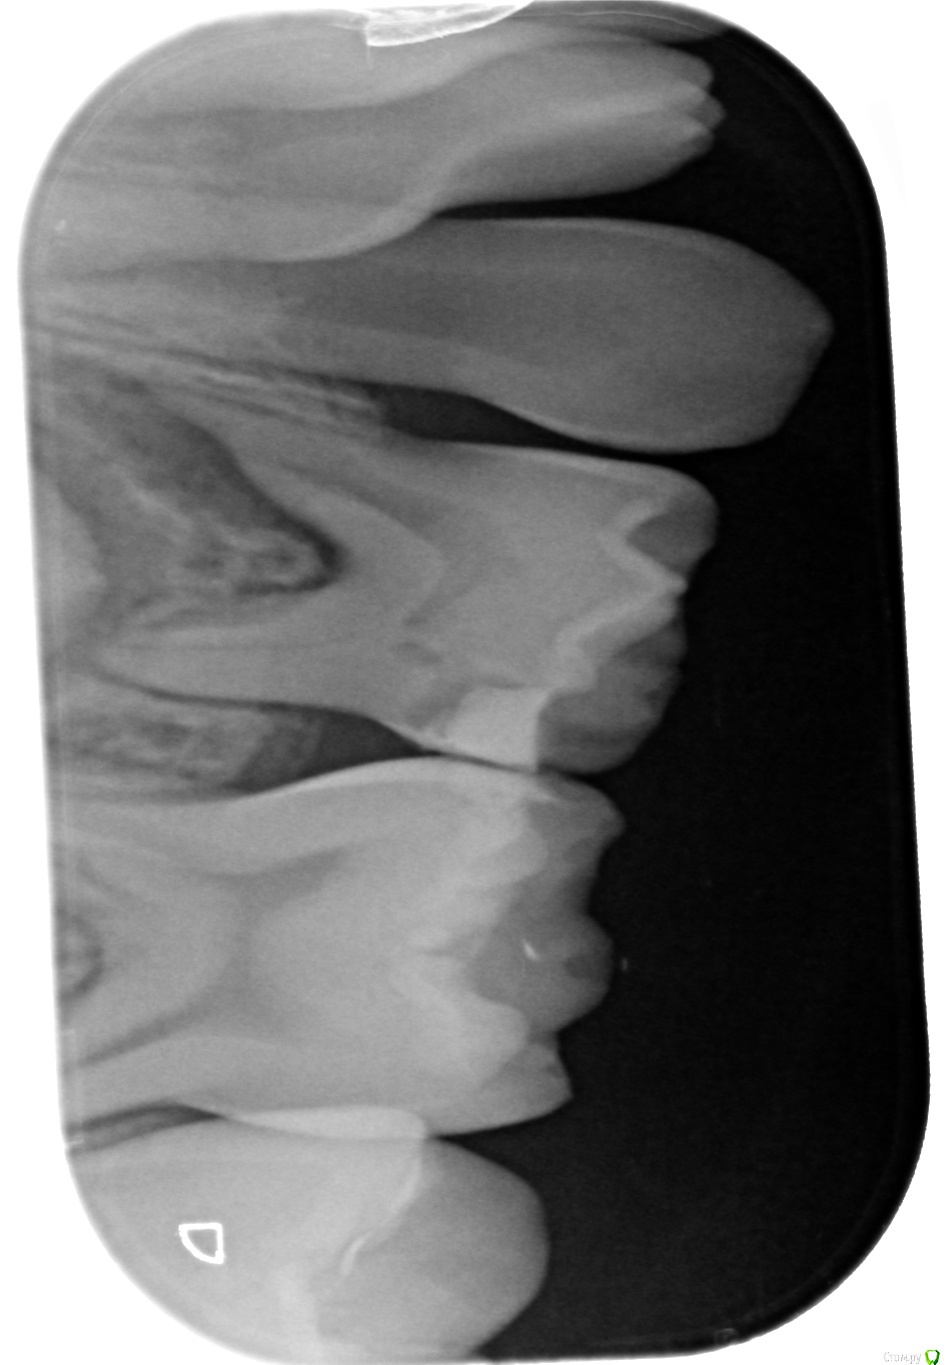

alezz Опубликовано 4 февраля, 2019 Поделиться Опубликовано 4 февраля, 2019 Вчера у ребенка разболелась десна и немного припухла щека. Сегодня были в клинике, врач после осмотра и рентгена сделала вывод что из-за неправильного пломбирования инфекция заразила нервы в трех молочных зубах и из них пошла в десну. Все зубы боковые, молары. Два рядом справа и один слева. Она мне показала рентгеновкие снимки, там действительно видно что корни у этих зубов сильно разрушились в сравнении с другими.Я предложил их просто вырвать. Но она сказала что ребенку еще только 7.5 лет, а постоянные зубы на этих позициях вырастают в 11 лет. Если их удалить, то другие молочные зубы сместятся и коренные потом неправильно вырастут. Она предлагает удалить пломбы, попробовать пролечить каналы и с новыми пломбами сохранить эти зубы хотя бы еще на год. Мне в этом во-первых не нравится то, что инфицированные зубы будут постоянным источником инфекции во рту. Она сама сказала, что полностью вылечить их уже не получится. И во-вторых просто не хочется платить за сложное лечение молочных зубов.Действительно ли настолько важно в 7,5 лет бороться за сохранение молочных зубов? Ссылка на комментарий

alezz Опубликовано 5 февраля, 2019 Автор Поделиться Опубликовано 5 февраля, 2019 Снимки Ссылка на комментарий

Дмитрий Л. Опубликовано 5 февраля, 2019 Поделиться Опубликовано 5 февраля, 2019 4е моляры молочные удалить, 5й можно попробовать отстрочить ненадолго Ссылка на комментарий